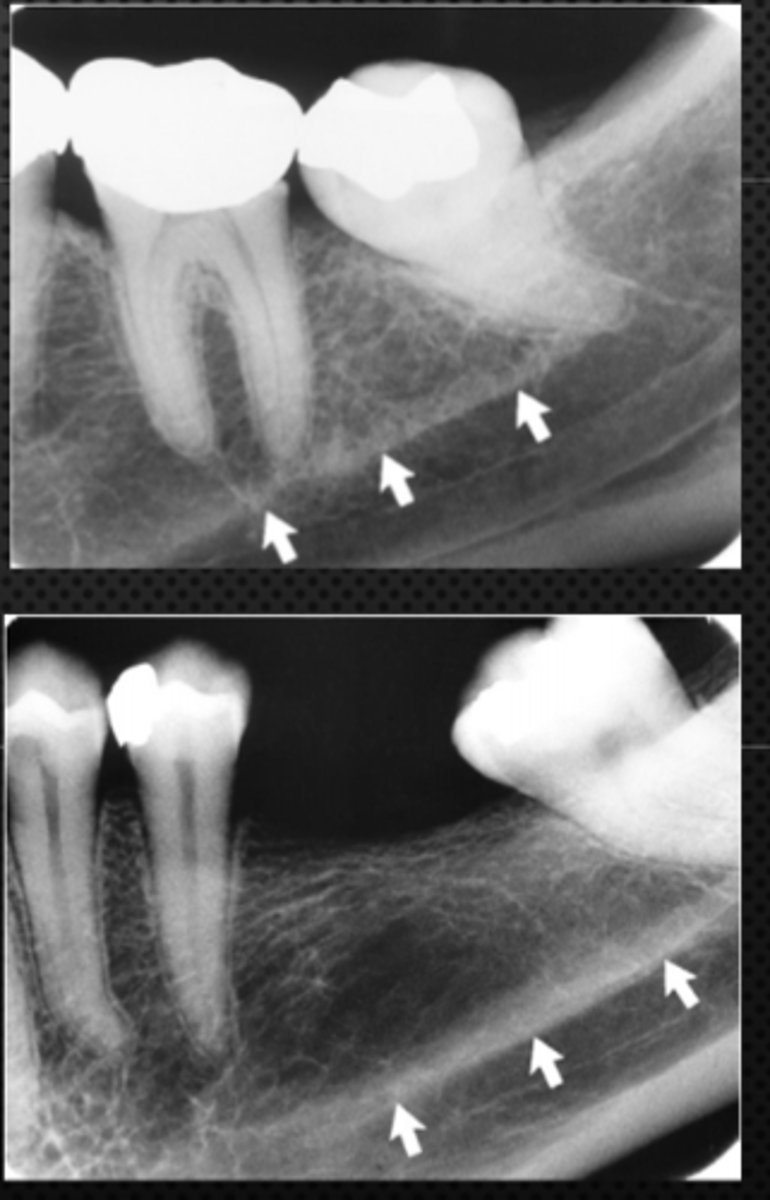

Submandibular fossa

Name the radiolucent area indicated by the arrows

<p>Name the radiolucent area indicated by the arrows</p>

Floor of nasal cavity

What does the line indicated by the arrows represent?

<p>What does the line indicated by the arrows represent?</p>

Mandibular canal

What is causing the thick radiolucent line surrounding the dotted line?

<p>What is causing the thick radiolucent line surrounding the dotted line?</p>